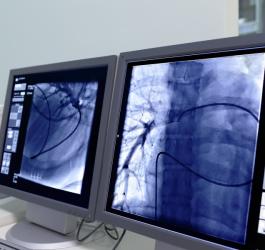

- Kardiologia